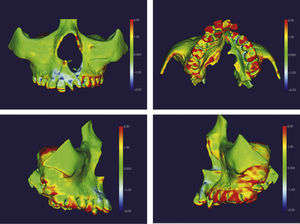

O surgimento e o aumento da acessibilidade da TCFC agregaram uma maior credibilidade ao diagnóstico clínico e às investigações científicas no estudo das deformidades craniofaciais19. Todavia, as informações 3D fornecidas pelas TCFC ainda vêm sendo rotineiramente analisadas de forma 2D, por medidas lineares em cortes ortogonais5,20. A construção e sobreposição de modelos virtuais 3D ainda é uma metodologia pouco difundida. Este estudo é um dos pioneiros que utiliza este método para avaliação de ERM em pacientes com fenda. A sobreposição baseia‐se na construção dos modelos virtuais 3D, utilizando o software SLICER21, pelos arquivos obtidos na TCFC, seguida pela sua justaposição, que utiliza a base do crânio como referência e a final obtenção dos métodos de medidas intitulados: sobreposição por semitransparência e mapa por códigos de cores22. A sobreposição por semitransparência revela uma análise qualitativa, em que o momento pós‐tratamento é retratado por uma malha preta translúcida, sobre o modelo inicial em vermelho (figs. 9 e 10). O aparelho em leque demonstrou um deslocamento de quase todos os dentes para vestibular e uma movimentação vestíbulo‐posterior do segmento menor (lado esquerdo [fig. 9]). O mapa por códigos de cores permite um complemento da análise visual, sendo que cada cor reflete uma alteração na posição das estruturas: azul – recuo; verde – estabilidade e vermelho – expansão. A intensidade da cor está diretamente relacionada à quantidade de movimentação. Todo o mapa é seguido por uma escala, com os valores em milímetros para cada cor (figs. 11 e 12). A observação feita na sobreposição por semitransparência do expansor em leque é confirmada no mapa por código de cores e nas medidas lineares. Uma menor porção de vermelho é visualizada em molares, quando comparada aos pré‐molares. O deslocamento para posterior e vestibular do menor segmento é constatado pela presença de azul na mesial dos dentes e vermelho nas eminências alveolares do lado em questão. Diferentes tonalidades de azul são vistas na cervical dos incisivos, possivelmente uma retroinclinação em decorrência da ausência de apoio mecânico no local. Para a quantificação das mudanças no posicionamento dentário, primeiramente identificou‐se, nos 3 cortes ortogonais, os pontos de referência para a medida (ponta da cúspide mésio vestibular dos primeiros molares superiores e ponta da cúspide dos caninos), tanto do lado direito como do lado esquerdo, utilizando o software ITK Snap23. Os pontos foram marcados com uma esfera de 0,5mm de diâmetro, identificando a posição 3D destas referências no espaço (fig. 13). A aferição das distâncias Euclidianas entre as esferas foi realizada com o auxílio da ferramenta Q3DC no programa SLICER23. O paciente A obteve um aumento de 3mm na distância intercanina e de 6mm na distância intermolar. Na elucidação do paciente que utilizou o disjuntor mini‐Hyrax invertido com BTP (B), observa‐se na sobreposição por semitransparência um deslocamento vestibular, principalmente dos pré‐molares e uma constância das demais áreas, achados corroborados no mapa por código de cores. A área que não está verde é a região de pré‐molares, vermelho por vestibular e azul por palatino, notando uma tonalidade entre verde e vermelho (amarelo) no corpo da maxila do lado menor (esquerdo). A oclusal dos molares, em vermelho, representa a erupção dos elementos.

Sobreposição com semitransparência dos modelos 3D do tratamento com o aparelho em leque. Antes da expansão representado por vermelho e após a expansão pela malha fina translúcida. Observa‐se um trespasse da malha preta para vestibular em molares, pré‐molares e canino, indicando que houve expansão em toda essa região.

Sobreposição com semitransparência dos modelos 3D do tratamento com o aparelho mini‐Hyrax invertido com BTP. Antes da expansão representado por vermelho e após a expansão pela malha fina translúcida. Observa‐se um trespasse da malha preta para vestibular na região dos pré‐molares, indicando expansão concentrada nessa região.

Os 2 casos clínicos aqui apresentados demonstram um efeito isolado da ERM em pacientes portadores de FLPMCU e não podem ser generalizados como comportamento esperado em ERM de pacientes com fenda. Todavia, é nosso objetivo demonstrar que o expansor em leque não correspondeu com sua indicação, apresentando um comportamento diferente do relatado na literatura24. A quantidade de expansão foi inesperadamente maior na região posterior em relação à anterior. Adicionalmente, objetiva‐se difundir na literatura outra opção terapêutica: o mini‐Hyrax invertido com BTP. Este aparelho correspondeu aos achados anteriores, priorizando a expansão anterior e com mínima, ou nenhuma, interferência em posterior. Demais estudos de ensaio clínico devem ser realizados, aperfeiçoando a metodologia e inserindo novas configurações de expansores maxilares, elucidando de forma embasada os efeitos de cada um. O modo de expansão desejada dita o aparelho a ser usado, e essa escolha afeta diretamente o tratamento e prognóstico do paciente.